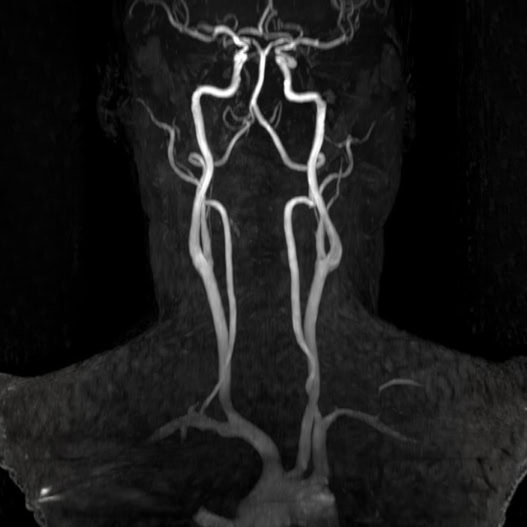

Conditions Detectable with Our Whole Body MRI

Whole Body Scan